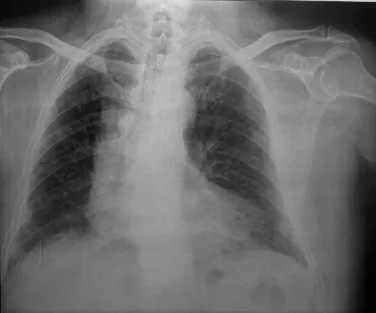

| CXR/CT | Upper lobe nodules, 'egg-shell' hilar calcification. PMF. | Upper lobe nodules. PMF (lesions >1cm). Caplan Syndrome (RA + nodules). ![]() |

Hilar 'egg-shell' calcification.